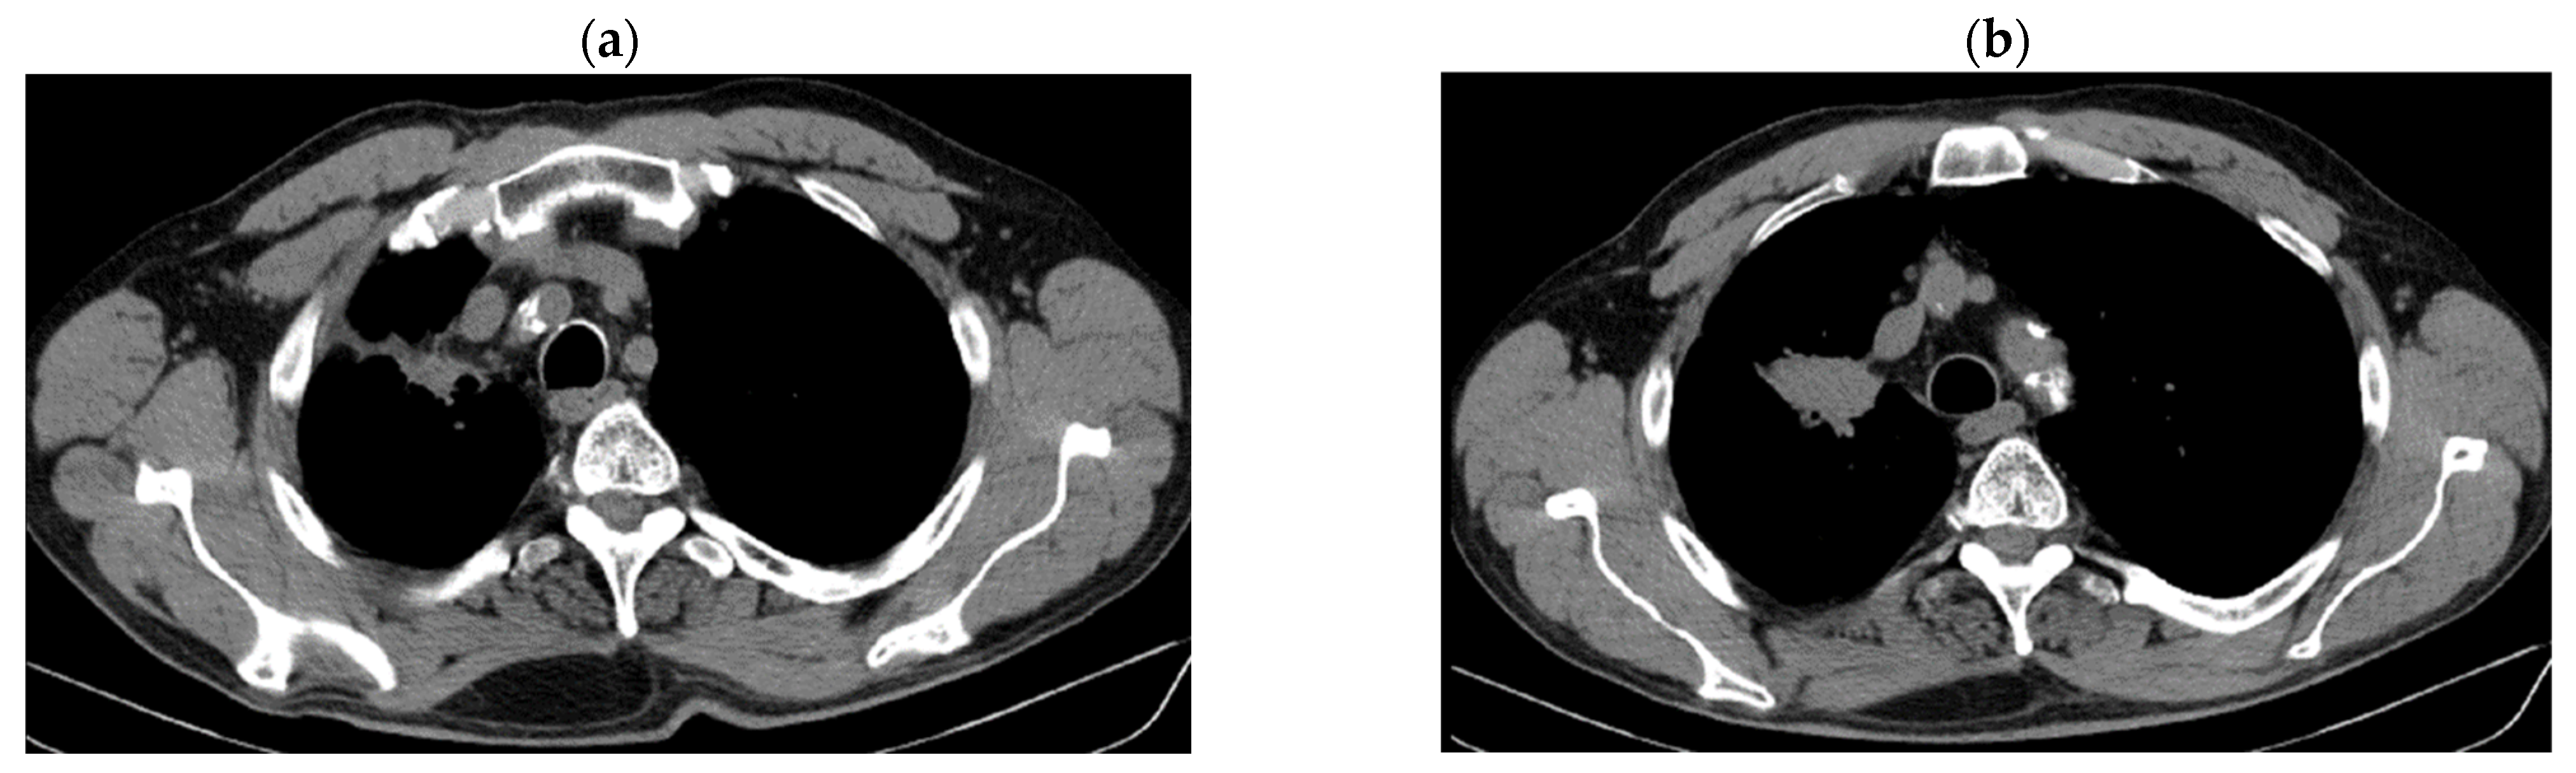

2.2. Monitoring 2022: Oncological Commission 1910/16.08.2022

2.3. Oncological Committee 07/25/2023 Recommended

- Consider rescue re-irradiation (SBRT), taking into account the current primary tumor dimensions of 24 × 34.2 mm on PET CT from 06/2023 and also the total dose previously administered (08–09/2020), the previously applied fractionation, the time between the two irradiations, the cellular repair time and the dose constraints for the organs at risk.